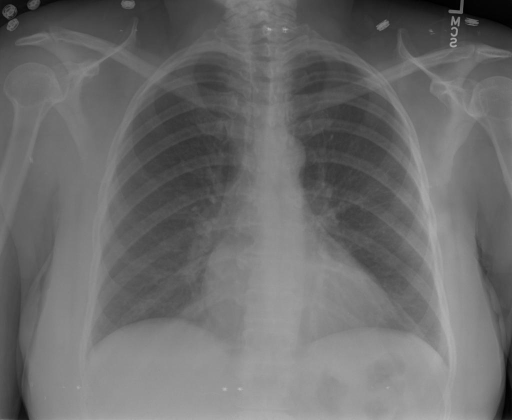

|X光影像|诊疗报告(医生)|XrayGLM|

||X光图片显示没有扭曲的区域、可疑的骨质不透明度或胸腺积液。心脏大小轻微增大,但非常稳定。此外,没有气胸的证据,肺野也正常。总体来说,X光片显示没有急性心脏异常,但要注意轻微的心脏扩大。|X光片显示,心脏大小正常。肺部和纵隔轮廓清晰,没有气胸或胸腔积液的证据。骨骼结构完整,没有任何急性异常。|